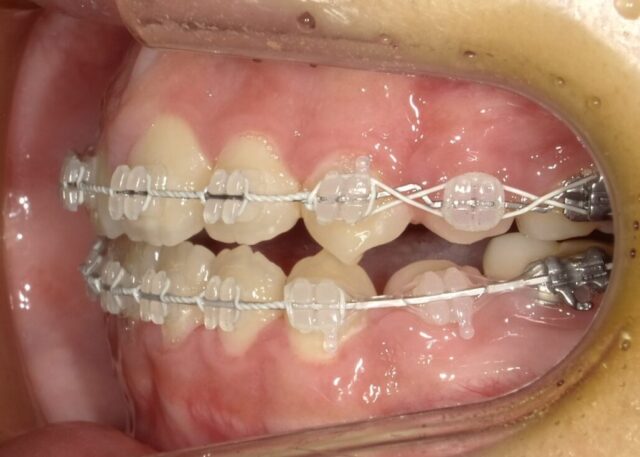

≪左側面観≫

2023年5月

2023年6月

2023年7月

2023年8月

2023年9月

2023年10月

2023年11月

2023年12月

2024年1月

2024年2月

2024年3月

2024年4月

2024年5月

2024年6月

2024年7月

2024年8月

2024年9月

2024年10月

2024年12月

2025年1月